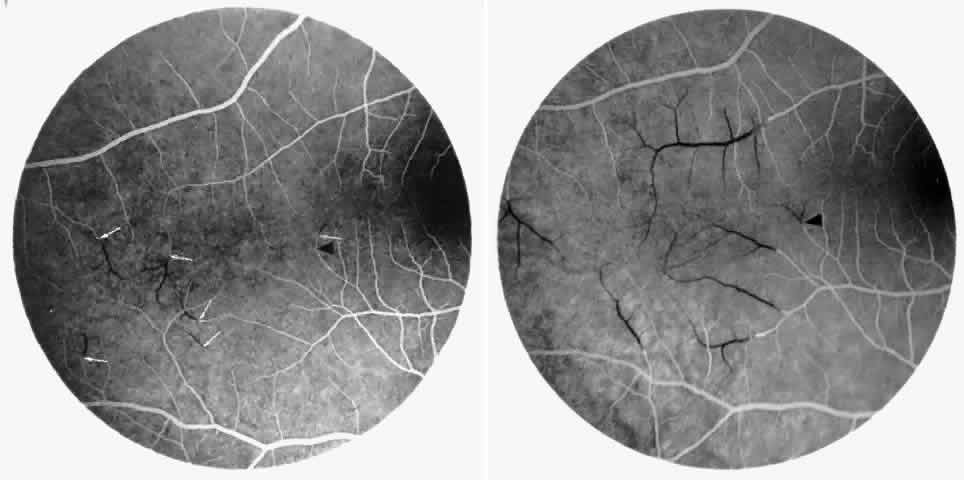

Occlusions of the fine vasculature of the macular and perimacular area have been reported in 10% to 40% of patients with sickle cell disease.18,83,91–99 In the acute phase, the occluded vessel will have a dark red appearance and may appear as a dark line on fluorescein angiography (Fig. 9). Nerve fiber layer infarcts (cotton-wool spots) are seen (see Fig. 8D and E;Fig. 10).100

Fig. 9. A 27-year-old man with homozygous sickle cell anemia. A. Fluorescein angiogram of the right eye shows multiple arteriolar occlusions temporal to the fovea (arrows). B. Same area 6 months later shows more extensive occlusions. The black arrowheads (A and B) identify corresponding arteriolar bifurcation.

Fig. 10. A 33-year-old woman with SC disease and stage III sickle cell retinopathy. A. Photograph of the right eye shows a cotton-wool spot with a dark segment identifying the occluded vessel (arrow). B. Fluorescein angiogram demonstrates nonfilling of the occluded vessel (arrow). C. Eighteen months later, the occluded vessel is still visible (arrow). D. Fluorescein angiogram demonstrates that there is still nonfilling of the vessel (arrow).

Other macular and perimacular changes include microaneurysm-like dots, dark and enlarged segments of arterioles, hairpin-shaped venular loops, pathologic avascular zones, and widening and irregularities of the foveal avascular zone (Figs. 11 and 12). In the Jamaican cohort study evaluating children with homozygous sickle cell anemia and SC disease between the ages of 5.0 and 7.5 years of age, no pathologic avascular zones could be identified despite a high incidence of peripheral vascular closure.31 In evaluating patients with homozygous sickle cell anemia, no relationship between ISC counts and macular abnormalities or visual acuity could be found.101 Using fluorescein angiography, investigators have found the foveal avascular zone to be significantly larger in eyes with clinical evidence of sickle cell maculopathy as compared with normal eyes and eyes without clinical evidence of sickle cell maculopathy.102–104

Fig. 11. A. A 40-year-old woman with homozygous sickle cell anemia. A fluorescein angiogram demonstrates multiple microaneurysm-like dots with fluorescein leakage, hairpin loop (arrowhead), pathologic avascular zones (arrows), and a widened, irregular foveal avascular zone (FAZ). B. Fluorescein angiogram of a 30-year-old woman with homozygous sickle cell anemia demonstrates multiple microaneurysm-like dots and a widened, irregular FAZ.

Fig. 12. A. Fluorescein angiogram of the left eye of a 40-year-old man with homozygous sickle cell anemia, demonstrating an irregular foveal avascular zone (FAZ), hairpin loops, and loss of the temporal capillary network. B. Fluorescein angiogram of the right macula of a 38-year-old woman with homozygous sickle cell anemia, showing an abnormal FAZ, hairpin loop (arrowhead), and pathologic avascular zones (arrows).